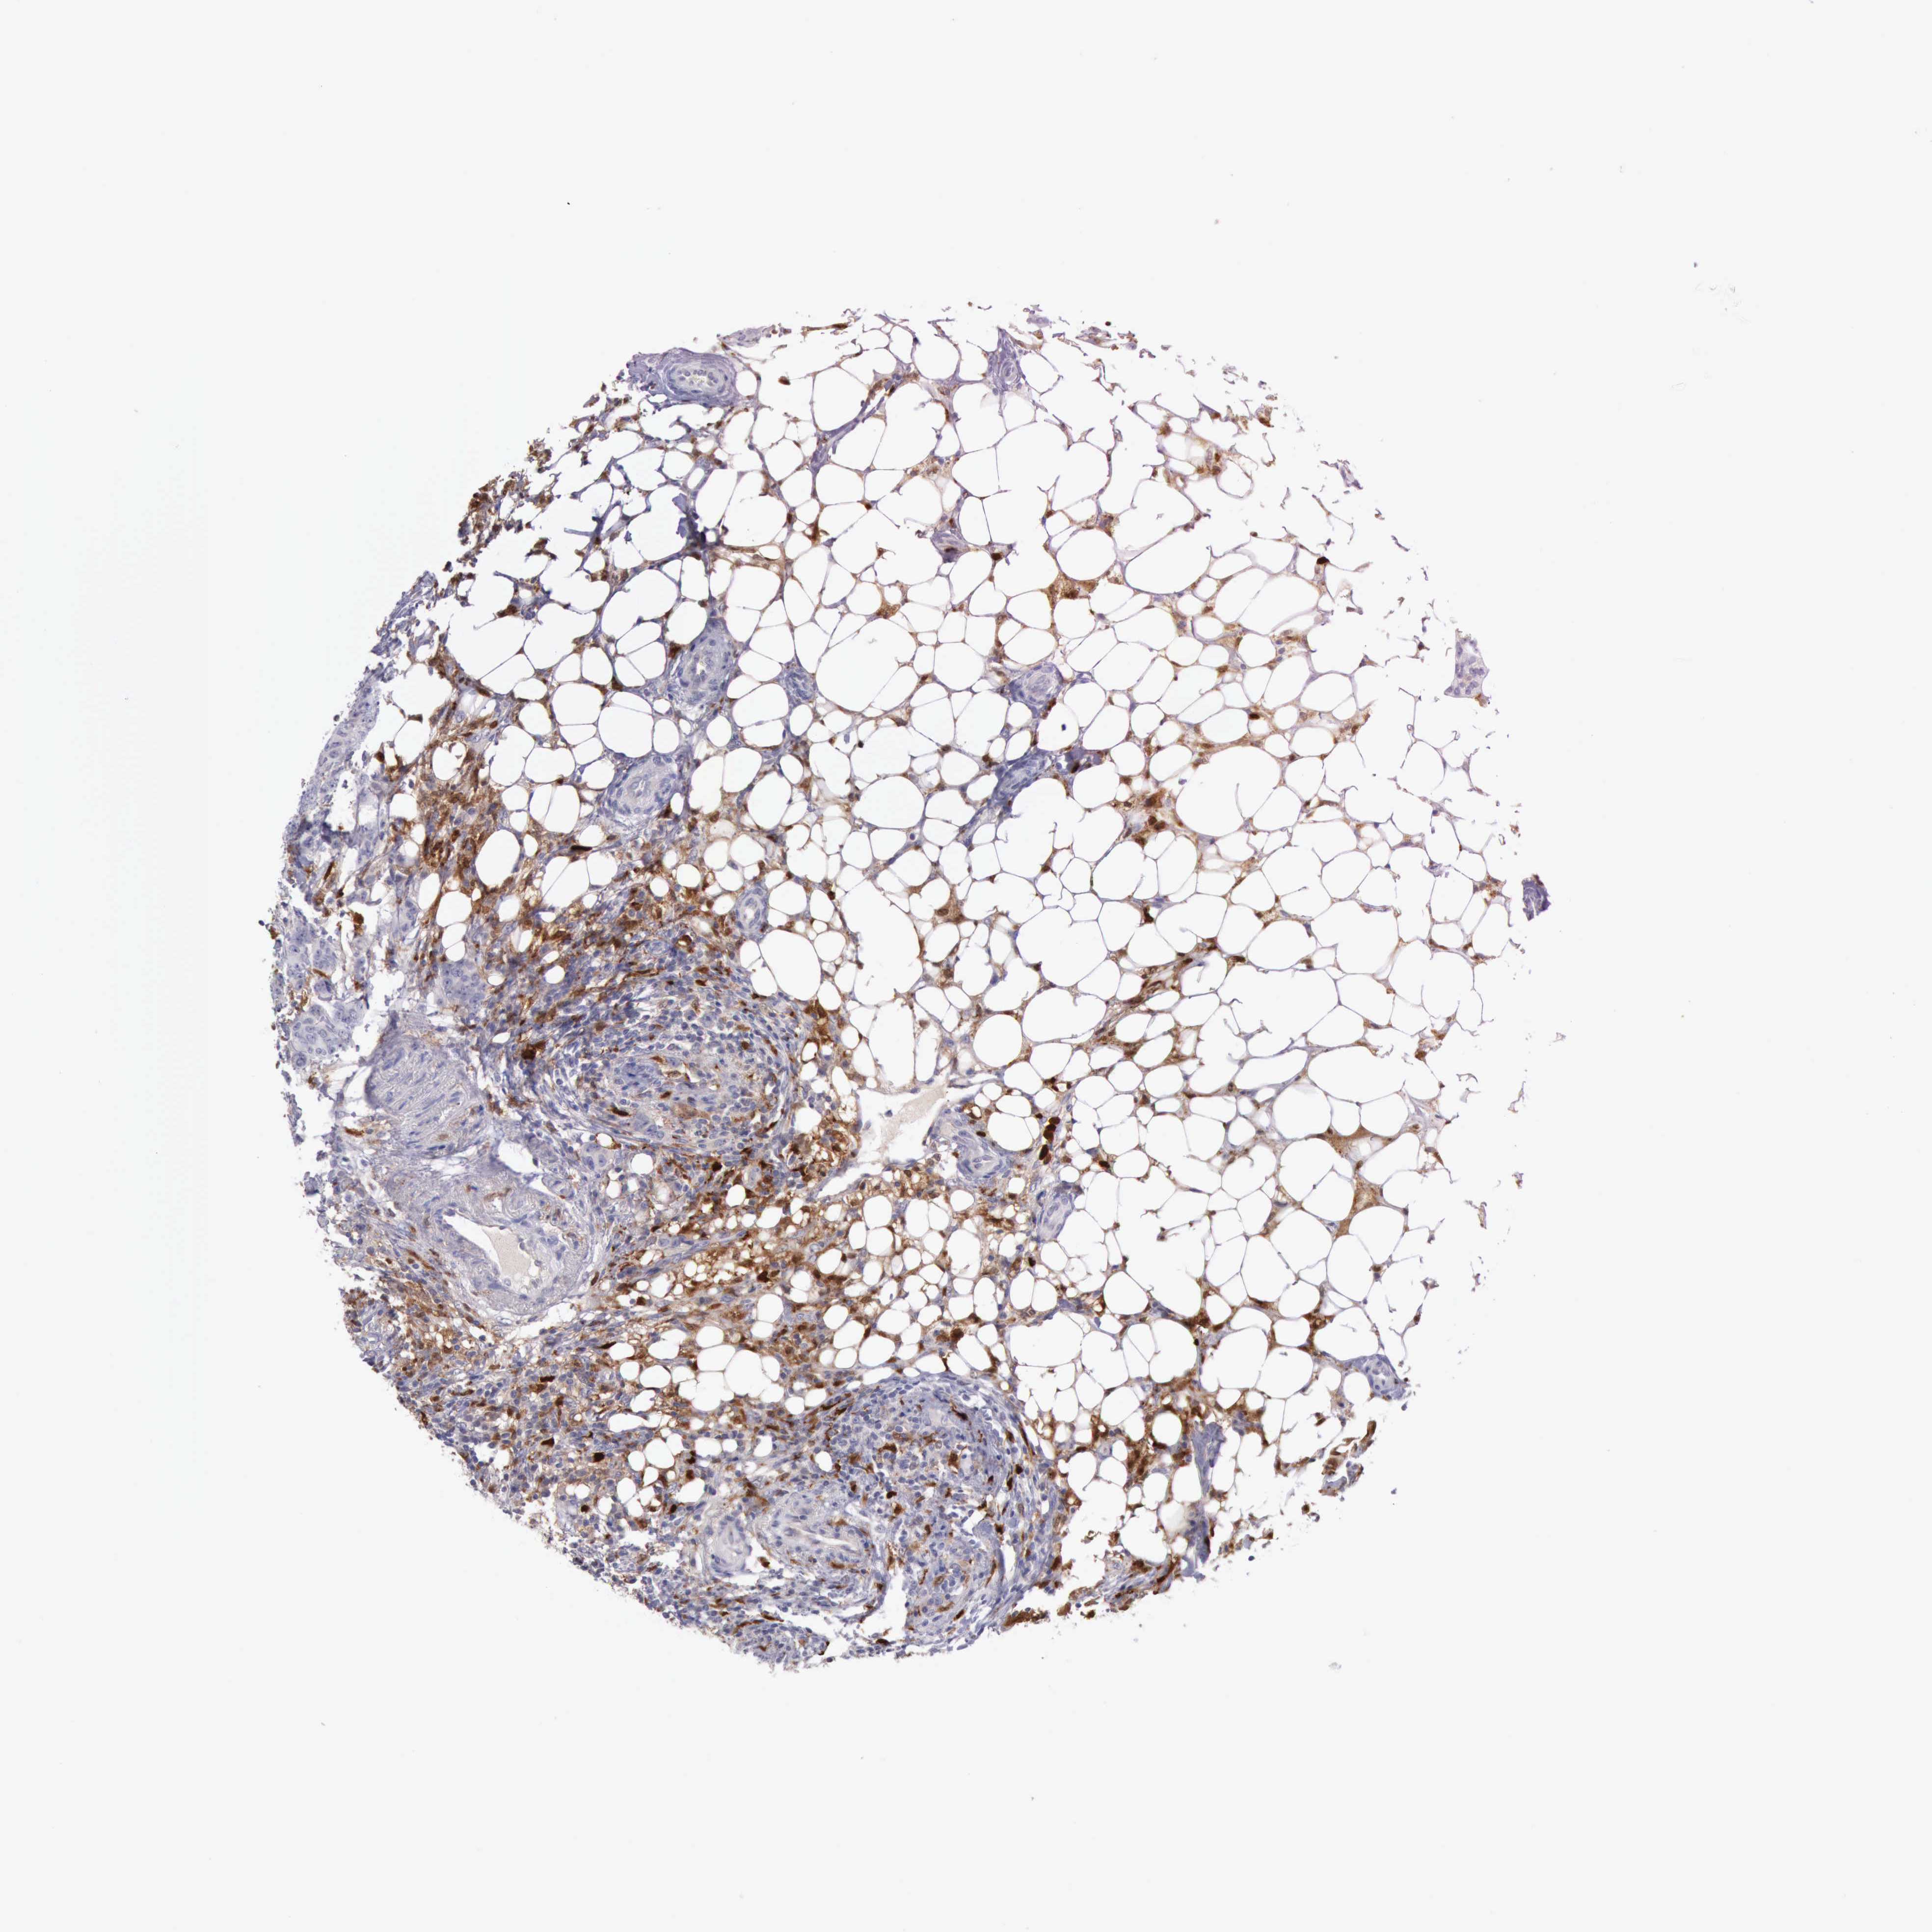

CANCER BREAST CANCER Show tissue menu

BRCA TCGA BRCA VALIDATION PROTEIN EXPRESSION